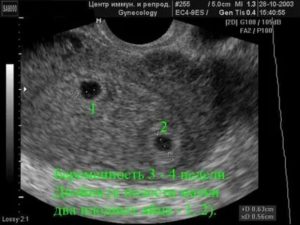

На каком сроке можно определить зарождение жизни? Сделать это можно и на первых неделях оплодотворения (на 3 неделе беременности), но результат может не оправдать ожидания. Поэтому лучше всего подождать и провести исследование согласно плану (на 10 неделе). Конечно, если на преждевременное обследование нет особых показаний по состоянию здоровья.

На каком сроке УЗИ покажет беременность? Первая плановая процедура проводится на 10 неделе интересного положения представительницы слабого пола. Но плодное яйцо можно рассмотреть уже спустя 5 дней отсутствия менструации. Какое УЗИ делают для распознания зачатия? Самый точный метод – трансвагинальный, но он проводится только при отсутствии противопоказаний.

Таким образом, на третьей гестационной неделе беременности на УЗИ видно плодное яйцо, хотя его размеры в это время очень маленькие. Получается, что если у женщины наблюдается уже 6 дней задержи, а она не знает на каком сроке можно определить беременность на УЗИ, то смело можно обращаться к своему гинекологу, который направит ее на такую диагностику.